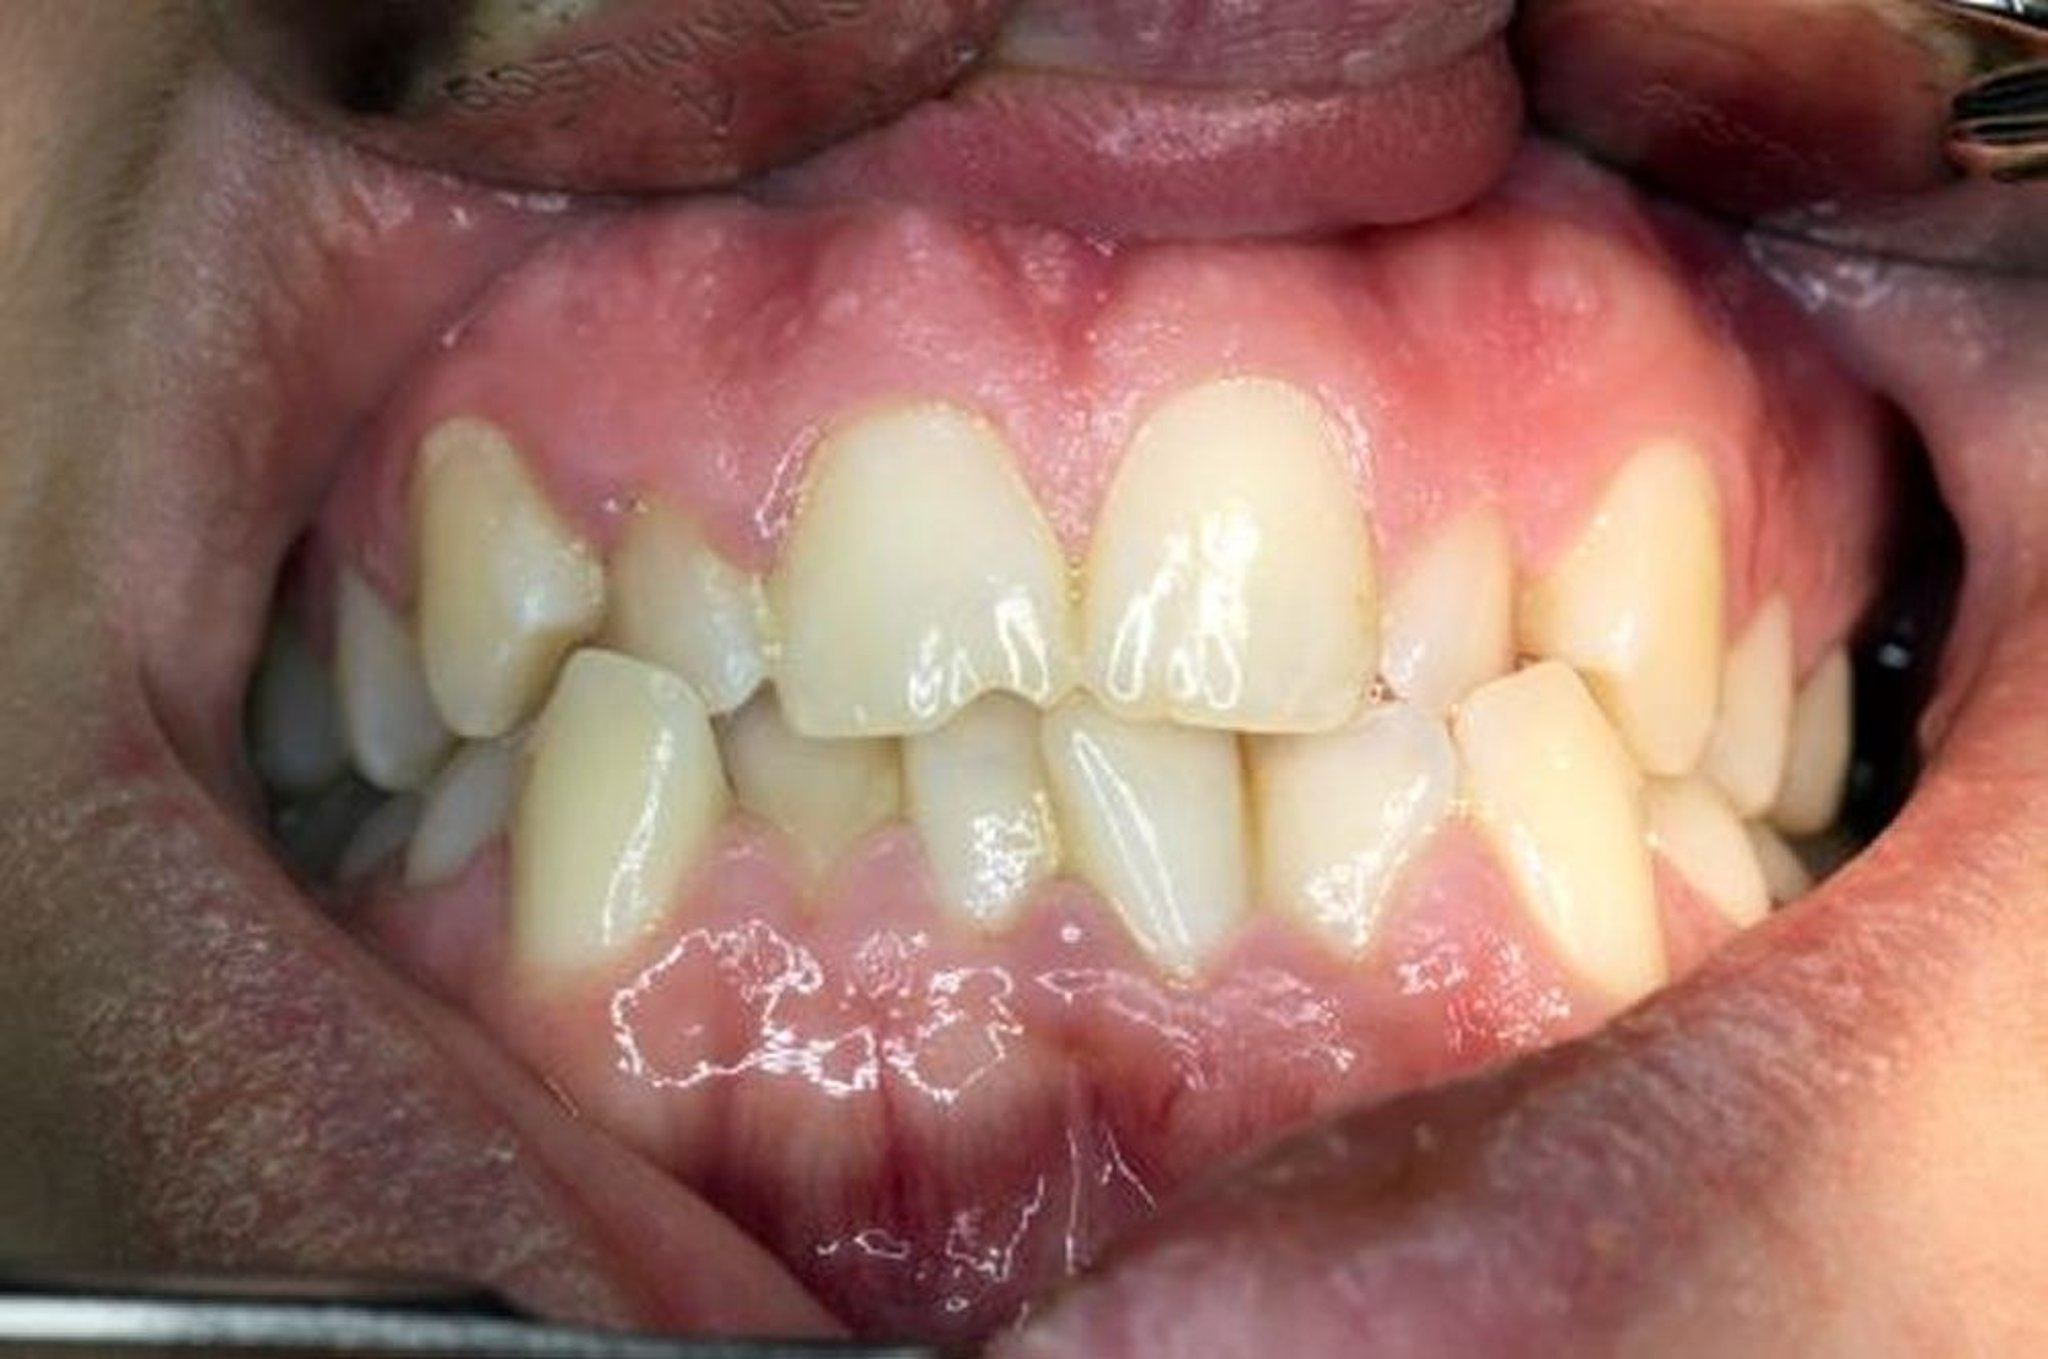

Malocclusione

I denti superiori e inferiori sono disallineati quando la mandibola viene chiusa.